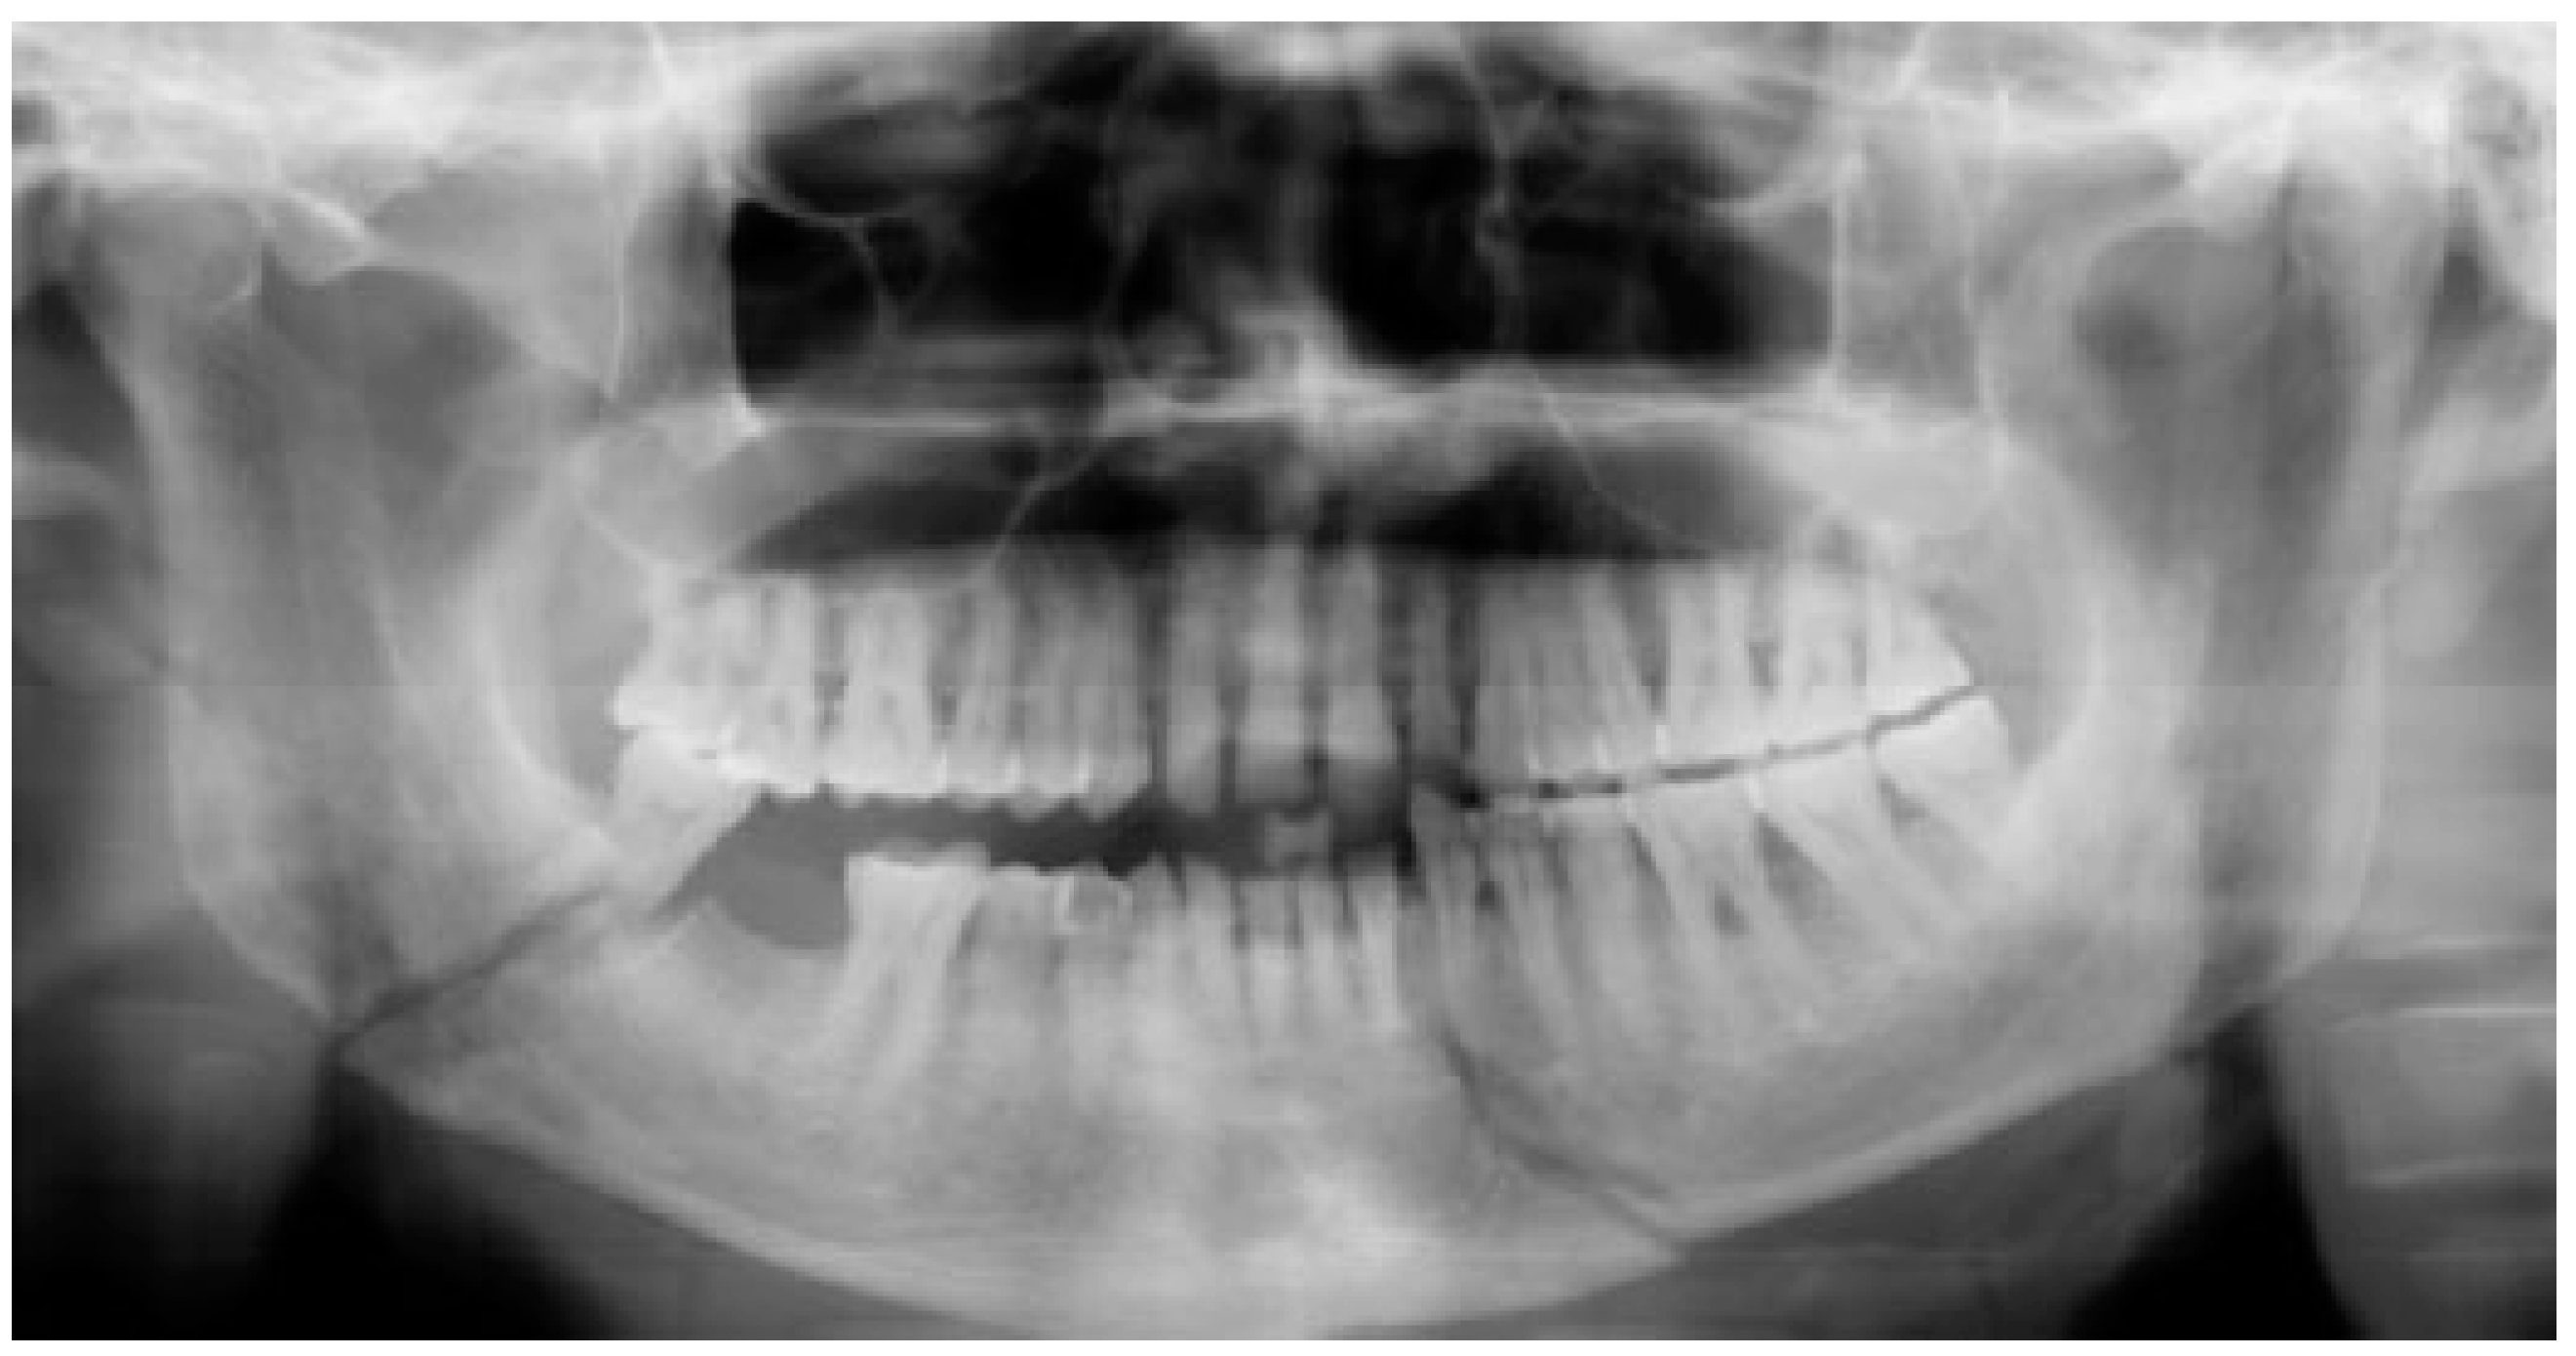

All the patients were treated by ORIF with the application of transient intermaxillary fixation using embrasure wiring [9] as intraoperative means of stabilizing occlusion along with 2.0 mm × 8.0 mm screws with 26-gauge stainless steel wire placed across the fracture line in mandibular angle to stabilize the fracture. Fixation of fracture was achieved using single 3D titanium locking miniplate placed with the help of transbuccal trocar or Synthes 90-degree hand piece and screw driver. The method of using transbuccal trocar or Synthes 90 degrees is totally dependenton thepersonal discretion of the surgeon. 3D locking titanium miniplates used in our study was four-holed, box-shaped plate, and screws with 2 mm diameter and 8 mm length. ORIF for all patients was done under general anesthesia with nasoendotracheal intubation (Figure 1 and Figure 2). Prior to the application of the 3D locking miniplates in the patients;, a prefabricated stereolithographic simulation replica model was made with the help of polymethyl methacrylate (PMMA) to help in contouring of the plate. Hence, simulation of the surgery was done beforehand to ensure the maximum adaptability of plate across the fracture line.

Figure 2. 3D locking miniplate used for fixation of right mandibular angle and left parasymphysis fracture.